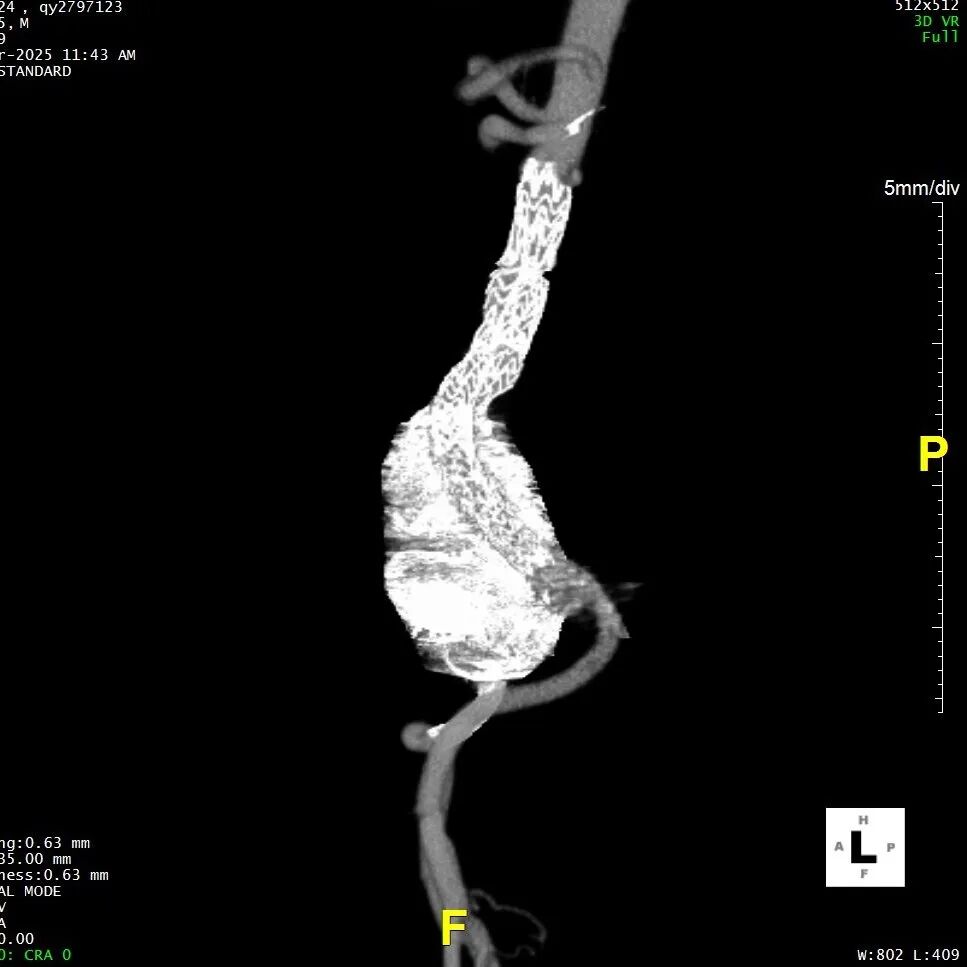

五、术后随访

患者术后进行随访,支架形态良好,瘤体隔绝良好,分支血管通畅,预后满意。

gore医疗怎么样「漫腹精论」髂合时宜 精益求精——双MOB球囊导管辅助腹主动脉覆膜支架急诊治疗破裂巨大髂动脉瘤_https://www.jmylbn.com_新闻资讯_第28张

gore医疗怎么样「漫腹精论」髂合时宜 精益求精——双MOB球囊导管辅助腹主动脉覆膜支架急诊治疗破裂巨大髂动脉瘤_https://www.jmylbn.com_新闻资讯_第29张

gore医疗怎么样「漫腹精论」髂合时宜 精益求精——双MOB球囊导管辅助腹主动脉覆膜支架急诊治疗破裂巨大髂动脉瘤_https://www.jmylbn.com_新闻资讯_第30张

gore医疗怎么样「漫腹精论」髂合时宜 精益求精——双MOB球囊导管辅助腹主动脉覆膜支架急诊治疗破裂巨大髂动脉瘤_https://www.jmylbn.com_新闻资讯_第31张

gore医疗怎么样「漫腹精论」髂合时宜 精益求精——双MOB球囊导管辅助腹主动脉覆膜支架急诊治疗破裂巨大髂动脉瘤_https://www.jmylbn.com_新闻资讯_第32张

gore医疗怎么样「漫腹精论」髂合时宜 精益求精——双MOB球囊导管辅助腹主动脉覆膜支架急诊治疗破裂巨大髂动脉瘤_https://www.jmylbn.com_新闻资讯_第33张

gore医疗怎么样「漫腹精论」髂合时宜 精益求精——双MOB球囊导管辅助腹主动脉覆膜支架急诊治疗破裂巨大髂动脉瘤_https://www.jmylbn.com_新闻资讯_第34张